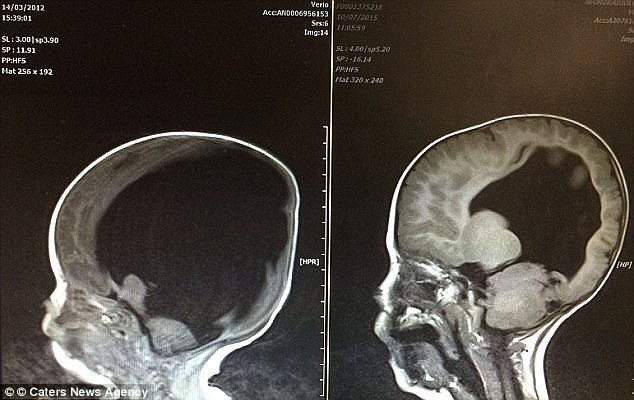

Hydrocephalus is a condition in which fluid builds up in the brain and in Noah’s case; the fluid buildup in his brain had destroyed all but 2% of his brain cells. Effectively, Noah didn’t have any brain left and since it is perhaps the most important organ in the body, which controls all the other organs. It also helps in development of other organs and helps in physical and mental growth of an individual.

In Noah, that would be impossible and therefore doctors didn’t have much faith in his survival. But miracles happen and in Noah’s case, he was born on this Earth to survive and that’s what he did. But his survival for four years and continuing has baffled the doctors.

Now four years old, Doctors are stunned to see Noah, who has even learnt to count. His brain has started growing and is almost to its full function. The spina bifida condition has however left him on a wheelchair.

"No one can explain how this recovery happened as it’s so complicated. He still has fluid on the brain - his latest scan doesn’t look like yours or mine. But the prognosis is good. He could become a doctor or Prime Minister. Intellectually, we will have to wait and see what he is capable of" said Dr. Colin Shieff, consultant neurosurgeon and trustee of brain injury charity Headway UK.